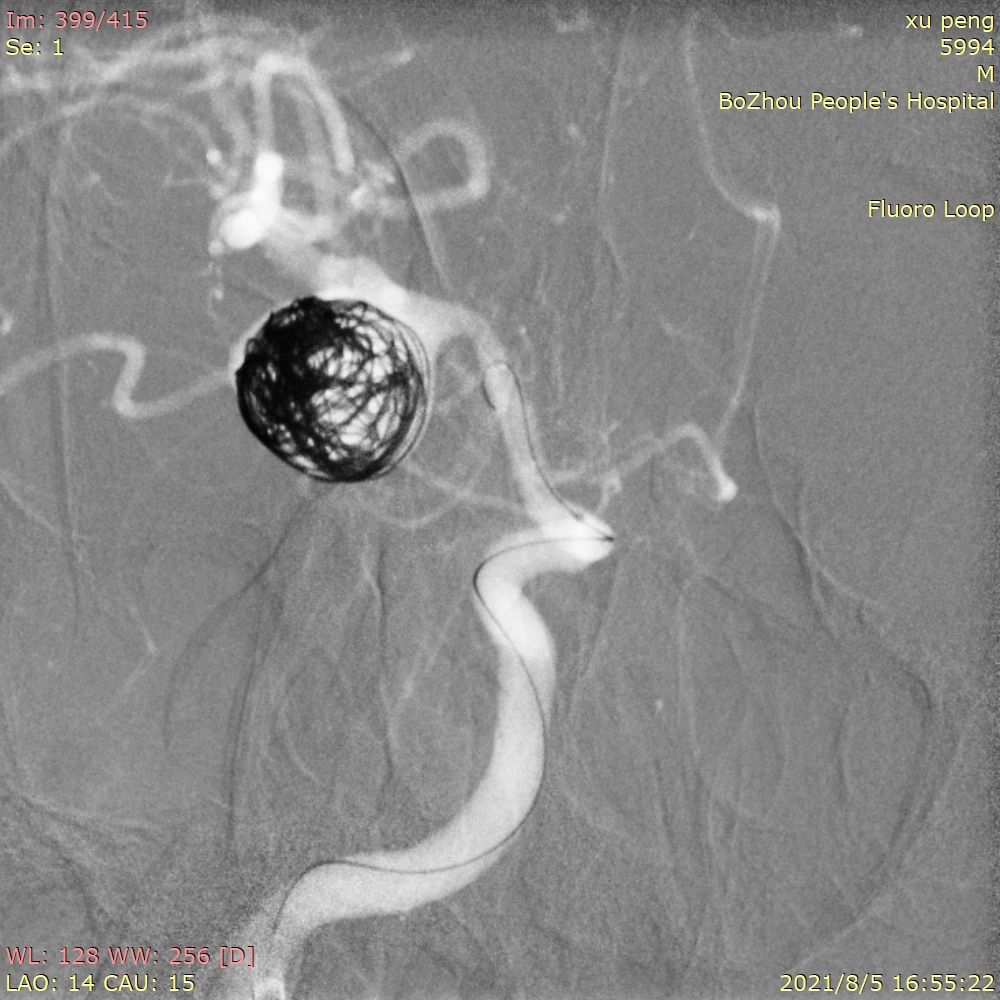

依次填入14/30、13/30、11/30、10/20*2弹簧圈后,发现第一根微导管已经基本固定在瘤颈上方,而瘤体中心及下方仍显影明显。这时我们暂不撤回第一根微导管,然后将第二根SL-10微导管塑形后送入瘤内下方继续填圈。

用两根微导管依次缓慢、小心填入9/30,8/30,7/20,6/20,5/10,3/8等圈,即刻造影,动脉瘤不显影,最终达到完全栓塞。

观察15分钟后再次造影,正位片。

观察15分钟后再次造影,侧位片。

载瘤动脉通畅,手术结束。